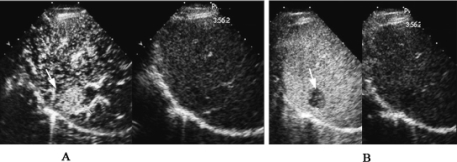

图23-15 原发性肝癌声像图

低回声型(肝右叶低回声包块)

1.肝脏内局限性异常回声区,边界清楚或不清楚,轮廓比较规则 其回声类型可有:低回声型(图23-15)、等回声型、高回声型(图23-16)、混合型等。混合型可为强弱不等回声,不均匀分布,或为内有液化坏死呈不规则无回声区。小肝癌多为低或等回声型,结节型及巨块型肝癌可为高回声或混合回声型。

2.病变与周围肝组织间多见“晕环征”,显示为低回声带(图23-16)